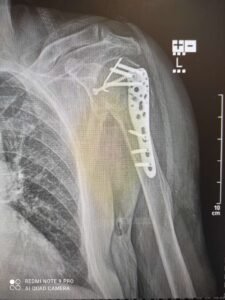

Під час чергового бойового завдання, отримав тяжке, кульове поранення лівого передпліччя, з багатоуламковим переломом променевої кістки та дефектом кісткових та мʼяких тканин. Насправді, я і подумати не міг що рука буде функціонувати, але завдяки професіоналізму лікарів, а саме Досяка Мирослава Ігоровича, він не тільки врятував руку, а і відновив її функції!